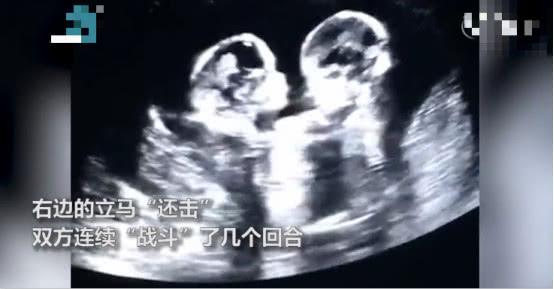

近日 , 网上有个搞笑的视频 , 引发大家的关注 。 视频中 , 宁夏银川的一女子怀了一对双胞胎姐妹 , 在宝宝3个月的时候 , 准时去医院做孕检 , B超显示两个宝宝竟然在妈妈肚子里打架 。

一开始是左边的宝宝先动手“打”了右边的宝宝一拳 , 右边宝宝随后立马“还击” , 两个宝宝就这样连续“战斗”了几个回合 , 这一幕引得医生和妈妈当场大笑 。 现在 , 这对双胞胎已经顺利出生 。